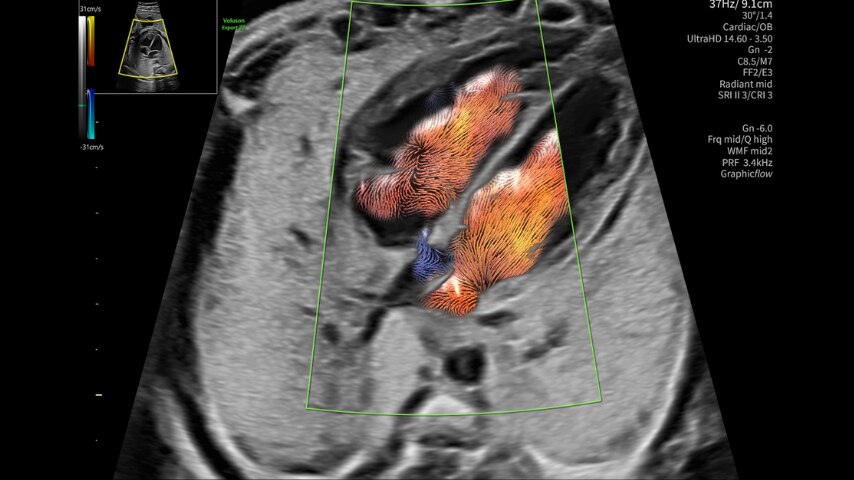

Neurografia